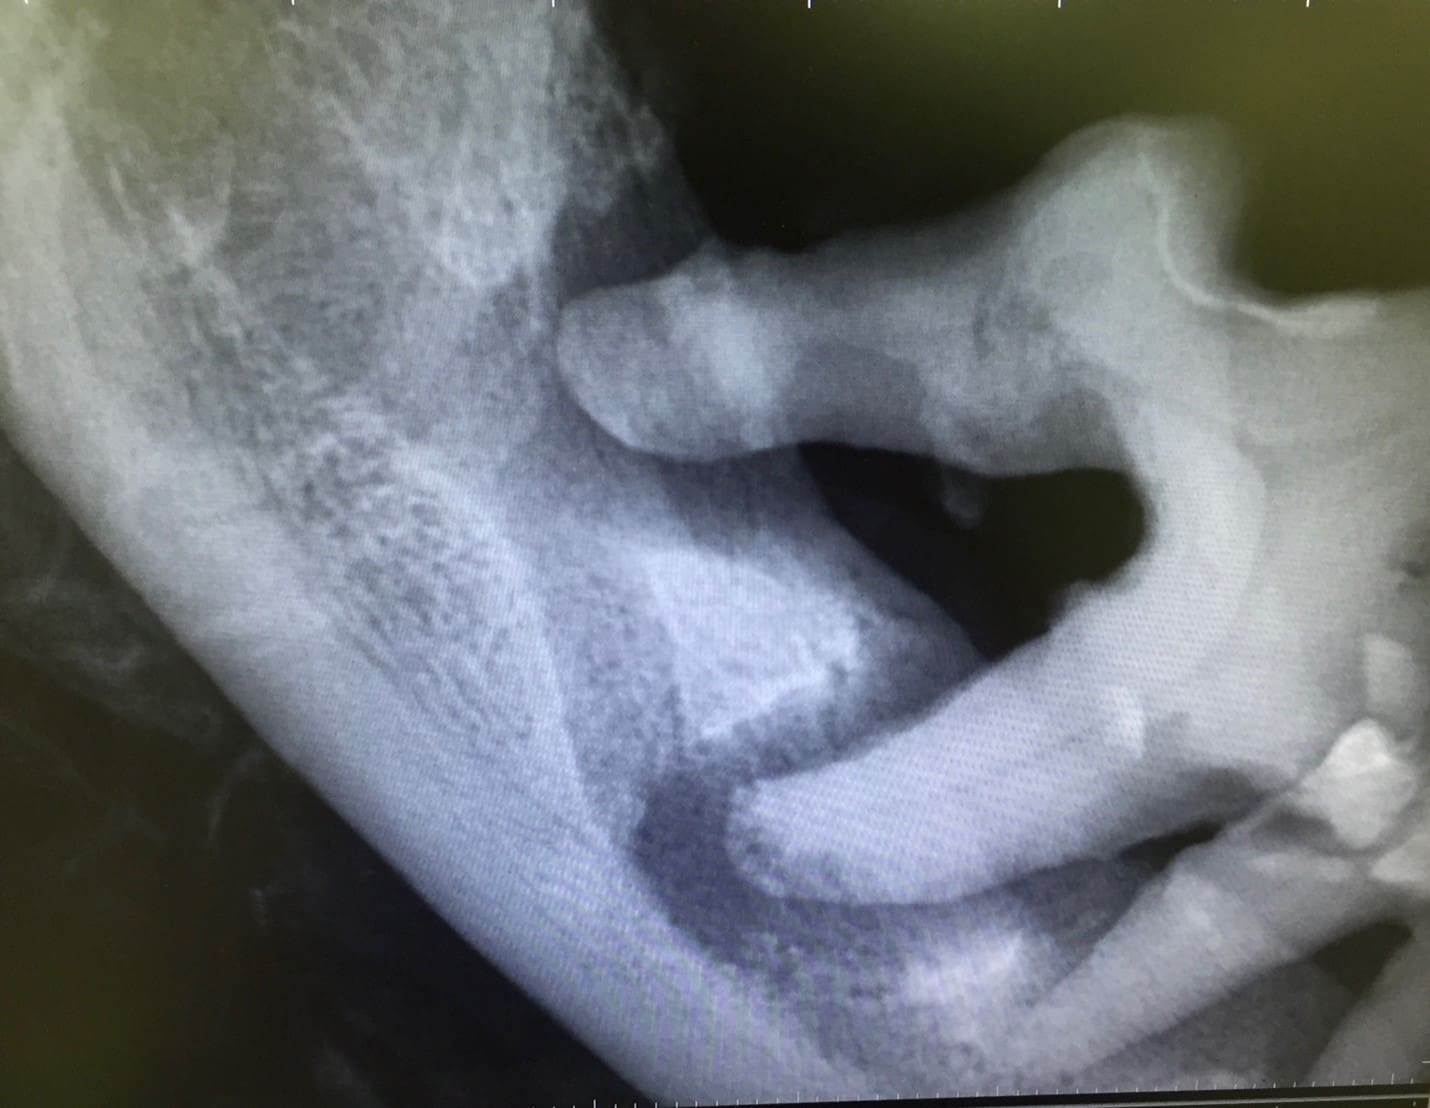

Specialty-level evaluation also includes advanced imaging, such as full-mouth intraoral radiographs and cone beam CT (CBCT), which allow precise assessment of attachment loss, furcation involvement, and areas of bone destruction that cannot be detected during a visual exam alone.

Untreated periodontal disease can result in serious and sometimes life-threatening complications. Severe bone loss around the maxillary canine teeth may result in an oronasal fistula, which can cause chronic nasal discharge or epistaxis. Advanced mandibular bone loss can significantly weaken the jaw, predisposing patients to pathological jaw fractures that may occur with minimal trauma.